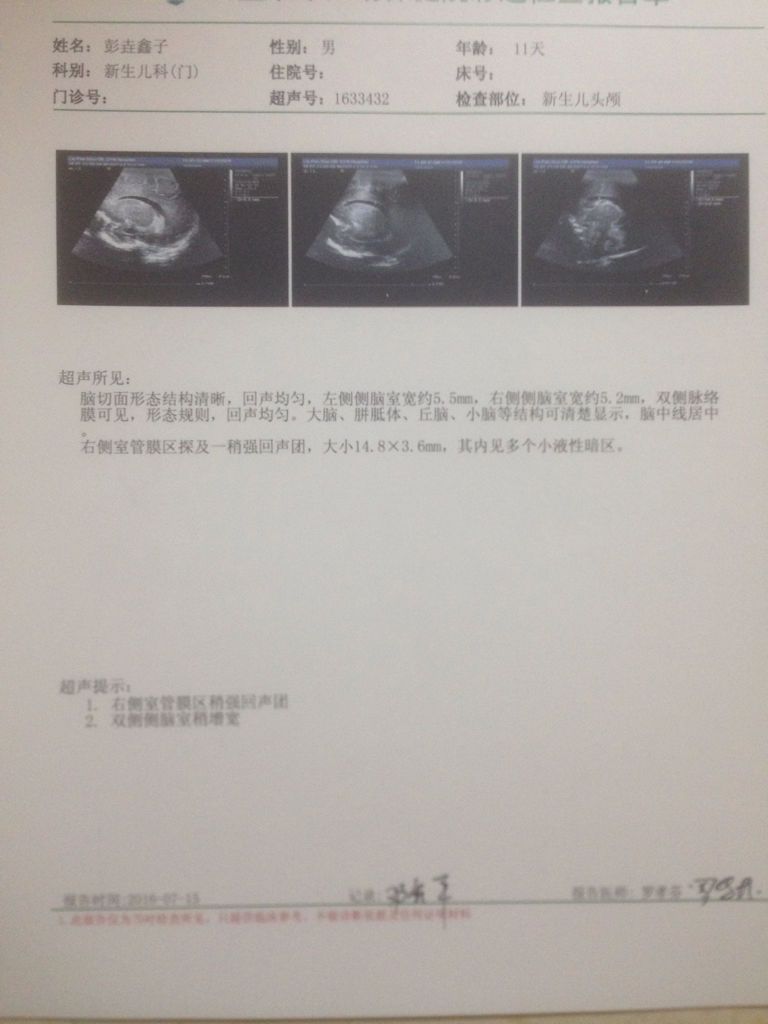

宝宝属于早产儿 33周加4天 已经生下来11天了 今天做脑部CT 结果不是太理想 请问下情况严重吗 点击展开 匿名用户 2016-07-15 22:36 满意回答 这种检查结果是B超检查,只是初殖栋府步的检查,确诊还是需要CT或磁共振检今旧查,如果现在孩子一般情况好,应梅卜该问题不大 zhixuping1 2016-07-15 22:41 宝宝知道提示您:回答为网友贡献,仅供参考。 相关问题 早产儿31周+5天今天做了CT发现脑部有 早产儿脑部CT结果!跪求!!! 早产儿脑部CT结果!跪求!!!